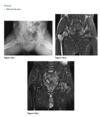

Figure 2.15.5, in which there is a

full-thickness ACL tear causing a double-PCL sign

(arrowheads) and a bucket-handle tear of the menis-

cus that is flipped anteriorly, causing an abnormally

tall meniscal anterior horn (arrow).